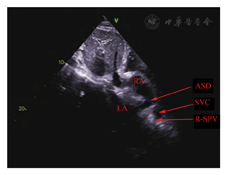

RA:右心房;LA:左心房;ASD:房间隔缺损;SVC:上腔静脉;R-SPV:右上肺静脉。剑下双房切面可见静脉窦型房间隔缺损和右上肺静脉引流至上腔静脉入右心房口部后壁